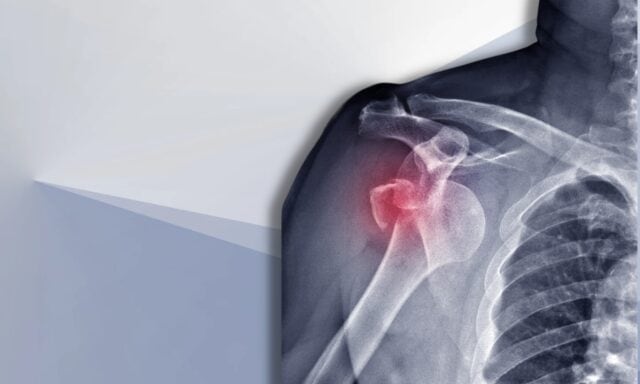

У овој епизоди ћемо причати о свим стварима нестабилности рамена. Сазнаћете више о Станморе класификацији и структурним оштећењима након дислокација. Разговараћемо о типичном пацијенту са нестабилношћу рамена и како изгледа процес прегледа. Дотакћемо се образаца активације мишића, хирургије и начина на који би физиотерапеутски третман пацијента са нестабилношћу рамена могао изгледати. Зато обавезно послушајте целу епизоду!